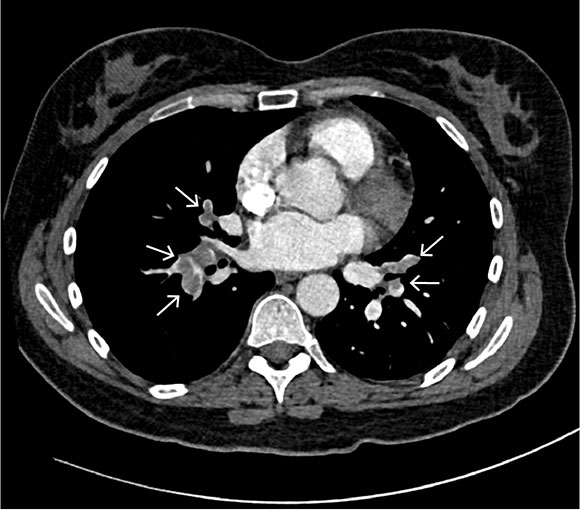

Ut fra arbeidsdiagnosen ble det gjort CT pulmonal angiografi, som viste lungeembolier i høyre hovedarterie samt segmentalt og subsegmentalt i lungearteriene bilateralt (figur 1). Både i høyre og venstre lunge ble det oppdaget basale, perifere, kileformede lungefortetninger som kunne indikere lungeinfarkter. Samtidig ble det påvist en lett utvidelse av truncus pulmonalis på 34 mm, som ytterligere støttet mistanken om forhøyet pulmonaltrykk og høyrebelastning.

Pasienten ble behandlet med lavmolekylært heparin i form av totalt 15 000 IE dalteparin subkutant for lungeembolier. Grunnet forhøyet kardial troponin T og tegn til høyrebelastning på CT angiografi ble hun overvåket med telemetri og videre henvist til transtorakal ekkokardiografi for vurdering av høyre hjertehalvdel. Denne viste normalt stor høyre ventrikkel med god funksjon, men med tegn til høyresidig trykkbelastning ut ifra noe forhøyet systolisk lungearterietrykk på 42 mmHg (< 35–40) og avflatet interventrikulært septum. Systolisk funksjon i venstre ventrikkel var normal, med en ejeksjonsfraksjon på 65 %.